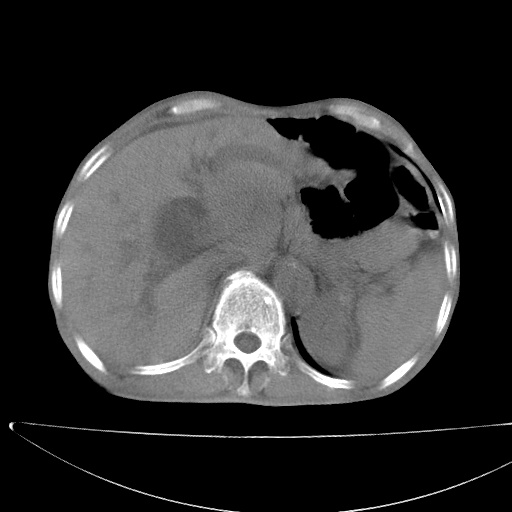

标题: CT17147:男70岁,上腹部不适1月。 [打印本页]

患者男70岁,上腹部不适1月。8年前有胃癌手术史。余病史不祥。

考虑胃癌复发并小网膜淋巴结转移侵及肝脏胆总管梗阻

考虑胃癌复发并腹腔内淋巴结转移。

1)胃癌术后,复发不排除。

2)肝脏转移瘤。

3)肝脏钙化灶。

4)胆囊增大。

5)腹膜后多发性淋巴结转移。

6)腹水。

7)右侧少量胸水。

建议:增强扫描。

1)胃癌术后,不排除复发可能。2)考虑肝脏及腹膜后淋巴结转移瘤。3)肝内胆管扩张,胆囊增大。4)肝内胆管结石(或钙化)。5)脾脏钙化灶。6)腹水。7)右侧少量胸腔积液。

建议:行ct增强扫描检查。

1、胃癌根治胃空肠吻合术后,残胃癌?

2、肝门区占位性病变并胆道上段梗阻(肝内胆管扩张、胆囊增大),考虑肝门区淋巴结转移累及胆总管,建议ct增强扫描;

3、右侧胸腔少量积液、少量腹水;

4、肝右叶胆管结石。